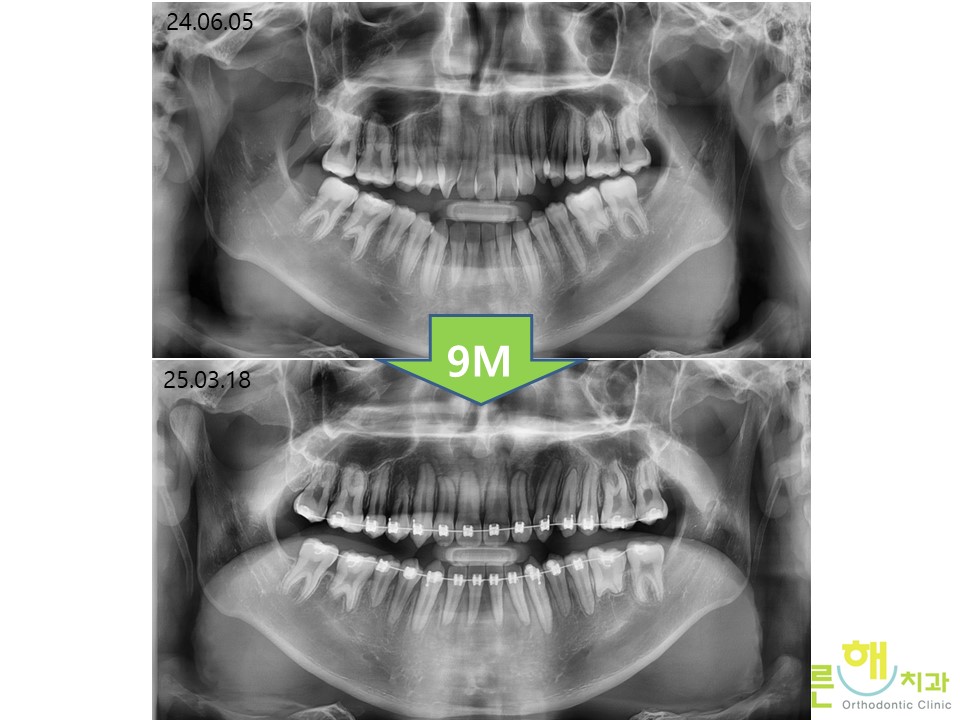

½ÉÇÑ ÅÎ ºñ´ëĪÀ» °¡Áö°í ÀÖ¾úÁö¸¸

¾ç¾Ç¼ö¼ú ¾øÀÌ ÅÎ ºñ´ëĪ ±³Á¤ Ä¡·á¸¦ ÅëÇØ

9°³¿ù ¸¸¿¡ Á¤»ó±³ÇÕÀ¸·Î °³¼±µÇ¾ú½À´Ï´Ù.

ºñ¼ö¼ú ÅÎ ºñ´ëĪ ±³Á¤ Ä¡·á 9´Þ

Á¤»ó ±³ÇÕÀÔ´Ï´Ù.

óÀ½¿¡ ½ÉÇÑ ÅÎ ºñ´ëĪÀ»

ÁÖ¼Ò·Î ³»¿øÇÏ¿´Áö¸¸

9°³¿ù ºñ¼ö¼ú ºñ´ëĪ Ä¡¾Æ ±³Á¤Ä¡·á¸¦

±¸°­±Ù±â´ÉÈÆ·Ã (MFT)¿Í ÇÔ²² ÇÏ´Â °ÍÀ¸·Î

ºü¸£°í °Ç°­ÇÏ°Ô ±×¸®°í ¾ÈÁ¤ÀûÀÎ ±³ÇÕÀÌ

Çü¼ºµÇ¾ú½À´Ï´Ù.

ÅÎ ºñ´ëĪÀÌ ºñ¼ö¼ú ºñ´ëĪ ±³Á¤Ä¡·á ¸¸À¸·Î

¸¹ÀÌ °³¼±µÈ °ÍÀ» º¼ ¼ö ÀÖ½À´Ï´Ù.

Ä¡¾ÆÀÇ °Ç°­ ¶ÇÇÑ ¾çÈ£ÇÕ´Ï´Ù.

¿·¾ó±¼ ¿¢½º·¹ÀÌ¿¡¼­´Â

ºñ¼ö¼ú ºñ´ëĪ Ä¡¾Æ±³Á¤Ä¡·á ÀüÈÄ·Î

½ºÅ©·ù³ª »ó¾ÇÈ®ÀåÀ» ÇÏÁö ¾Ê¾ÒÁö¸¸

ÅÎ ±æÀ̰¡ ª¾ÆÁö¸é¼­

¾çÈ£ÇÑ °³¼±ÀÌ ÀϾ °ÍÀ» º¼ ¼ö ÀÖ½À´Ï´Ù.